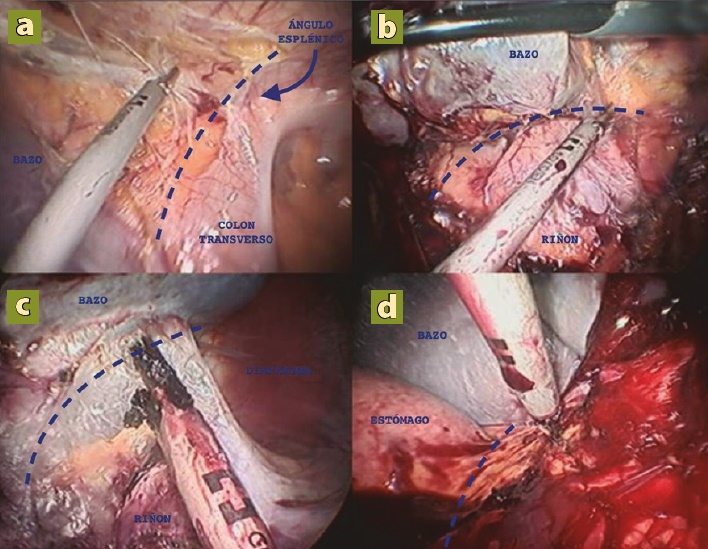

Se realizó laparoscopía diagnóstica y se inició disección del bazo liberando ligamentos lienocólico con energía ultrasónica (figura 5a), al igual que los ligamentos esplenorrenal (figura 5b) y esplenofrénico (figura 5c) y gastroesplénico (figura 5d). Se continuó la disección del hilio esplénico colocando grapas de titanio en la vena esplénica, y ligadura con nudo extracorpóreo con sutura monofilamento no absorbible de la arteria esplénica (figura 6). Se realizó la extracción completa de la pieza quirúrgica ampliando la incisión del puerto de trabajo. Se revisó la cavidad por tejido esplénico accesorio sin identificar, se verificó hemostasia y se colocó drenaje en lecho quirúrgico exteriorizándolo por incisión en línea axilar posterior.

Figura 5 a) Disección ligamento lienocólico, b) esplenorrenal, c) esplenofrénico y d) gastroesplénico. Todos los ligamentos mencionados están señalados en la imagen por la línea punteada (- - - - -).